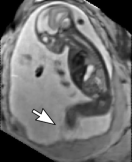

During image acquisition the fetus is not sedated and moves freely as well as the mother breathes normally. As a result, movements are likely to corrupt the scans, hiding pathology and causing overlap between different anatomical regions. In order to limit these artifacts, fast scanning sequences such as ssFSE [10] allow for the rapid acquisition of single slices at high in-plane resolution in a large field of view and good tissue contrast of the uterus. However, when acquiring a 3D volume through a stack of slices, inter-slice artifacts in the out-of-plane views are highly likely. Consequently, this restricts reliable diagnostics to individual slices in the current clinical practice. Fig. 1 depicts a typical example of motion related artifacts in a fetal single-shot fast spin echo (ssFSE) scan. The observed motion (c.f. Fig. 1 b & c) is of unpredictable nature and consists of a combination of maternal respiration movements, fetal movements and bowel movements.

Reconstruction of Fetal Organs: Exemplary PVR and SVR reconstructions under motion introduced by kicking of the fetus are shown in Fig. 11. PVR reconstruction results show an improved visual appearance and less blurring in the region with severe motion artifacts (arrow). An example of a challenging clinical case with a kidney malformation in one of twin fetuses, is shown in Fig. 8. Our clinical partners confirmed that such complications are easier to examine and to quantify after PVR-based reconstruction.